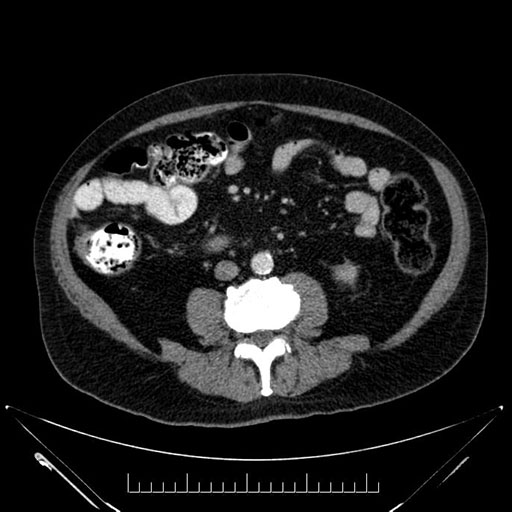

Whipple (pancreaticoduodenectomy) [case 7]

Coronal - stented

Based on your CT findings, which issue(s) would give reason for "planned slowing down moment(s)" in this case?

Considering a standard Whipple procedure, what step(s) of the operation would you do differently in this case?